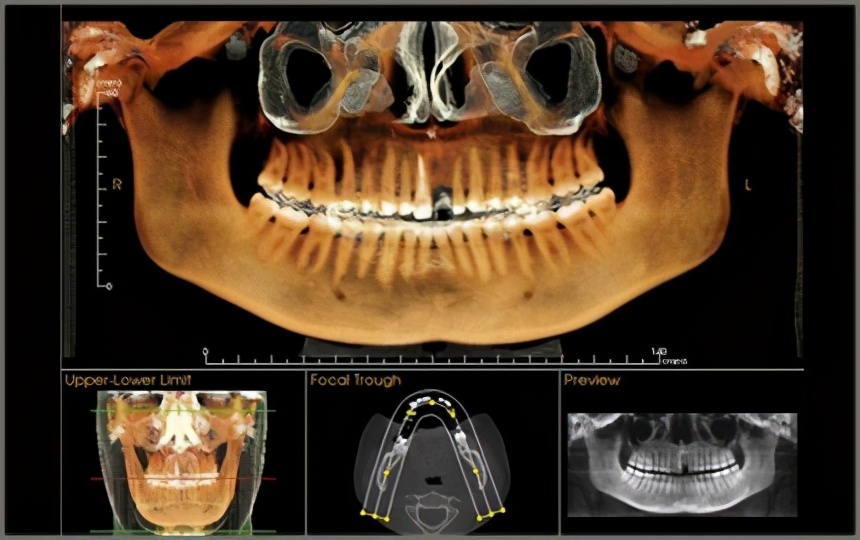

(CT影像)

或直接拍 CBCT ,就是我们常说的CT,也是300元不到,它是三维成像,非常立体呈现你牙齿的情况(上图有)。